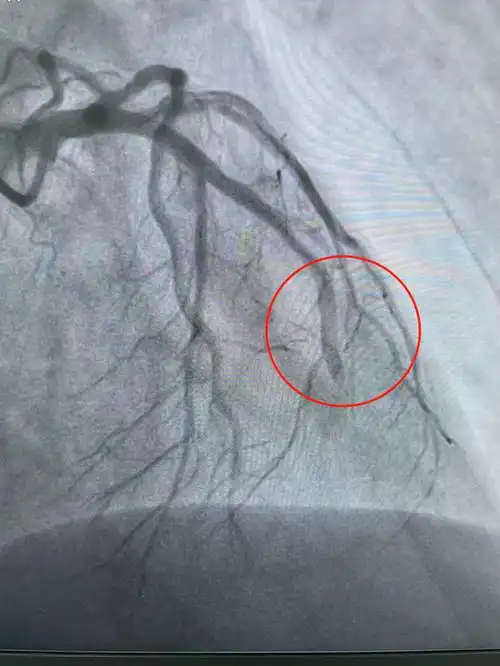

术前患者前降支血管完全闭塞

患者术前前降支闭塞